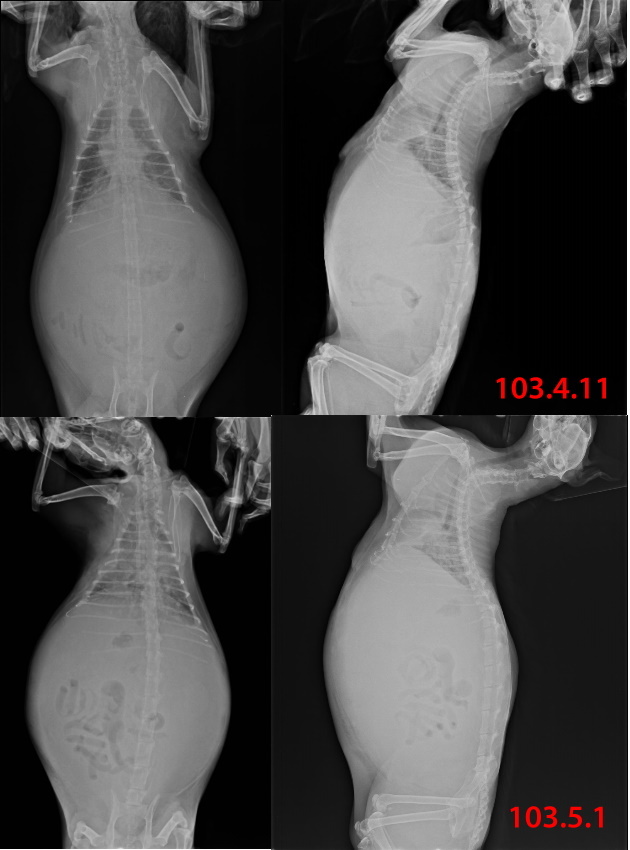

貓至醫院後(102.5.6),馬上安排檢查,發現不只乳腺腫瘤問題,腹腔也有疝氣及卵巢腫瘤,一並給予手術切除及治療,在醫院休養了二個月,因腫瘤為惡性,有擴散現像,並不適合再野放,通知志工,安排接出院安置後續照顧。

從102.5.6就醫出院後,一直在志工家安寧照顧,103年4月11日揪咪出現呼吸急促的狀況,緊急送醫血檢數值不佳,胸腹水瀰漫,抽出800CC暫時減緩呼吸不順的問題,出院後安至於安養之家,每天給與好多好多各式各樣的罐罐,看揪咪大口大口吃好滿足,5月1日,揪咪再度出現呼吸不順的狀況,送醫X光檢查又出現大量腹水,很遺憾腹水產生的速度太快太快,5月7日揪咪在姨姨的臂彎中安詳的離開,很謝謝"醫"路上有大家的扶持,能夠讓揪咪有一年快樂的時光,醫療的目的是為了獲得更好的生活品質,揪咪有家、有愛她的姨姨、還有醫路上的各位...